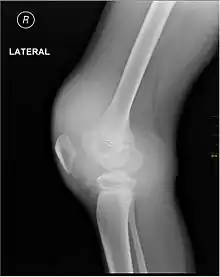

Synovial Fluid analysis is another method to diagnose Hemarthrosis. It involves a small needle being inserted into the joint to draw the fluid.[7] Reddish-colored hue of the sample is an indication of the blood being present. Imaging tests are normally done. The tests also include MRI, Ultrasound and X-ray test, which give better information about the joint inflammation.[8]